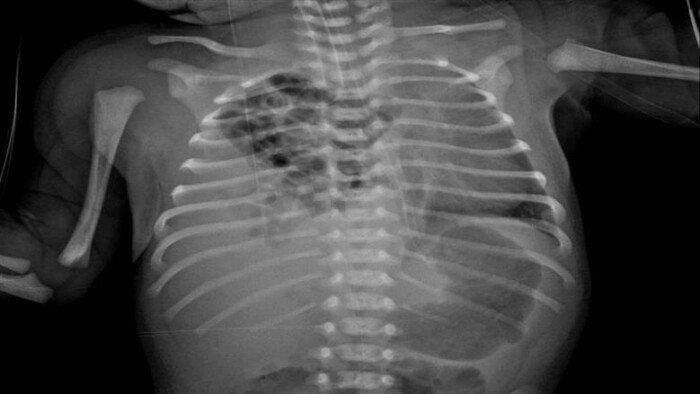

نجح الفريق الجراحي بمستشفى زاوية الناعورة المركزي في محافظة المنوفية، بقيادة الدكتور مجدي لولح والفريق المعاون، تحت إشراف الدكتور إسلام الفقي مدير المستشفى، في إجراء عملية نادرة لإصلاح فتق بالحجاب الحاجز من نوع «بوكدالك» في الجهة اليمنى، وهي من الحالات شديدة الندرة التي لا تتجاوز نسبتها عالميًا 10- 15% من إجمالي حالات الفتق الحجابي الخلقي.

وأشارت مديرية الصحة في بيان، إلى أنه تبيّن وجود الفص الأيمن من الكبد داخل التجويف الصدري إلى جانب الأمعاء الدقيقة والغليظة، مما تسبب في ضغط على الرئة اليمنى، وعلى الفور قام الفريق الطبي بإرجاع جميع الأعضاء إلى وضعها الطبيعي داخل تجويف البطن، ثم إصلاح الفتق بخيوط غير قابلة للذوبان من نوع «إيثيبوند» لضمان المتانة واستقرار الحالة.

وتابعت مديرية الصحة، أن الجراحين في المستشفى لاحظوا وجود التصاقات وأغشية تليفية من نوع «لادز» أدت إلى التواءات بالأمعاء، فتم التعامل معها بتقنية إصلاح «لادز» الجراحية، والتي شملت إزالة الأغشية التليفية، وإعادة ترتيب الأمعاء الدقيقة إلى الجهة اليمنى والقولون إلى الجهة اليسرى، مع استئصال الزائدة الدودية كإجراء وقائي.